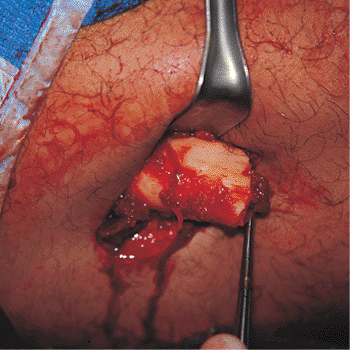

for proper nail placement and fracture reduction. A longitudinal

incision 6 to 10 cm is made over the greater trochanter and in-line

with the femur (Fig. 21.10). The fascia overlying the abductors is incised, and the muscle is split in-line with its fibers down to the piriformis fossa (Fig. 21.11).

![]() |

|

Figure 21.10.

Surgical incision planning. A 6- to 10-cm longitudinal incision is made just proximal to the tip of the greater trochanter. To accommodate distal locking, the surgical field must include the distal femur. |

Figure 21.11.

Incision and dissection. The incision has been made and the dissection carried through the subcutaneous tissue and the fibers of the gluteus maximus down to the posterior edge of the gluteus medius. The tip of the greater trochanter and the piriformis fossa are localized by digital palpation. |